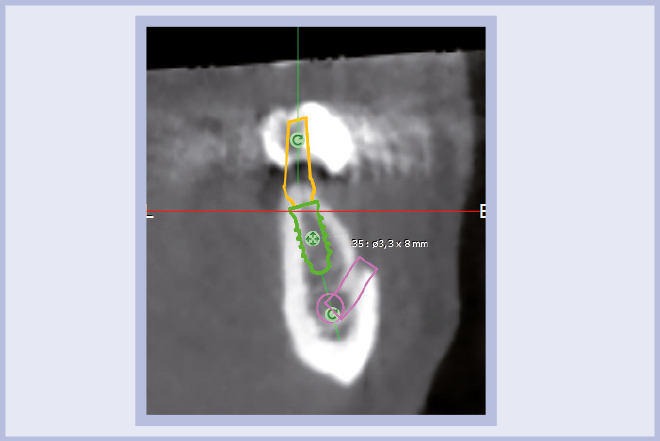

Per riabilitare la masticazione del terzo quadrante, con osso gravemente atrofico, si procede allo studio del caso con esame radiologico 3D e posizionamento virtuale di impianti Exacone® Leone. La prima valutazione è stata eseguita con il software dell’apparecchio radiografico Cone Beam presente in studio. Dopo aver verificato che la quantità di osso residuo fosse sufficiente all’inserimento di due impianti, seppur di dimensioni ridotte, in sede 3.5 e 3.6 senza l’ausilio di tecniche di rigenerazione ossea (Figg. 1-3), si richiede al laboratorio di confezionare una mascherina radiologica con ceratura diagnostica radiopaca e repere standardizzato a livello incisale come da protocollo Leone (Figg. 4, 5). Si verifica quindi clinicamente l’assenza di mobilità della mascherina dopo il posizionamento nel cavo orale del paziente (Figg. 6, 7). Si effettua una CBCT con la mascherina in posizione e l’esame viene inviato in formato DICOM all’azienda Leone assieme al modello master della paziente. L’azienda provvede quindi ad inviare agli Autori il software 3Diagnosys (software di progettazione) in licenza monopaziente con caricati i file DICOM ricevuti; il software viene quindi utilizzato per la progettazione definitiva del caso (Figg. 8-12).

- Figg. 1-3 – Esame Cone Beam iniziale, si verifica la fattibilità di inserimento impianti

- Fig. 2 mento impianti

- Fig. 3